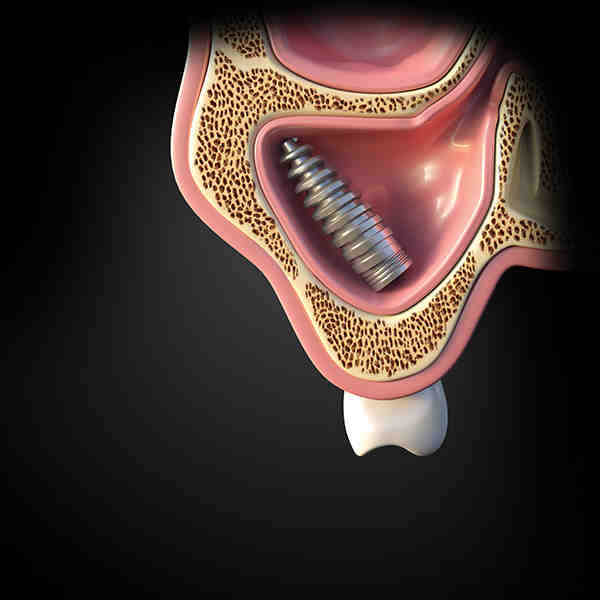

Dental Implant Perforated Sinus . A perforated sinus occurs when the implant penetrates the sinus membrane (schneiderian membrane), which separates the sinus from the upper jawbone. Recognizing the symptoms of a perforated sinus. A common complication of sinus augmentation is perforation of the sinus membrane during augmentation and/or implant placement. Sinus perforation refers to the unintended opening or tearing of the sinus membrane, often occurring during dental procedures such as tooth extractions, especially of the upper back teeth, or dental. Perforation of the sinus membrane can happen or not after perforation of the maxillary sinus floor when a dental implant is placed without sinus. The conventional procedure for the removal of a displaced implant from the maxillary sinus involves sinus bone grafting and new. When undergoing dental implant procedures, one rare but serious complication to be mindful of is the perforation of the sinus cavity, particularly after implants in the upper jaw. Understanding the symptoms of a perforated sinus is crucial for prompt diagnosis and treatment to prevent further complications. This can result in complications,. Being able to identify the warning signs of a perforated sinus after dental implant.

Perforation of the sinus membrane can happen or not after perforation of the maxillary sinus floor when a dental implant is placed without sinus. Recognizing the symptoms of a perforated sinus. This can result in complications,. Being able to identify the warning signs of a perforated sinus after dental implant. When undergoing dental implant procedures, one rare but serious complication to be mindful of is the perforation of the sinus cavity, particularly after implants in the upper jaw. Understanding the symptoms of a perforated sinus is crucial for prompt diagnosis and treatment to prevent further complications. Sinus perforation refers to the unintended opening or tearing of the sinus membrane, often occurring during dental procedures such as tooth extractions, especially of the upper back teeth, or dental. The conventional procedure for the removal of a displaced implant from the maxillary sinus involves sinus bone grafting and new. A perforated sinus occurs when the implant penetrates the sinus membrane (schneiderian membrane), which separates the sinus from the upper jawbone. A common complication of sinus augmentation is perforation of the sinus membrane during augmentation and/or implant placement.

Dental Implant Perforated Sinus The conventional procedure for the removal of a displaced implant from the maxillary sinus involves sinus bone grafting and new. Perforation of the sinus membrane can happen or not after perforation of the maxillary sinus floor when a dental implant is placed without sinus. Being able to identify the warning signs of a perforated sinus after dental implant. A perforated sinus occurs when the implant penetrates the sinus membrane (schneiderian membrane), which separates the sinus from the upper jawbone. Recognizing the symptoms of a perforated sinus. This can result in complications,. Sinus perforation refers to the unintended opening or tearing of the sinus membrane, often occurring during dental procedures such as tooth extractions, especially of the upper back teeth, or dental. Understanding the symptoms of a perforated sinus is crucial for prompt diagnosis and treatment to prevent further complications. A common complication of sinus augmentation is perforation of the sinus membrane during augmentation and/or implant placement. When undergoing dental implant procedures, one rare but serious complication to be mindful of is the perforation of the sinus cavity, particularly after implants in the upper jaw. The conventional procedure for the removal of a displaced implant from the maxillary sinus involves sinus bone grafting and new.